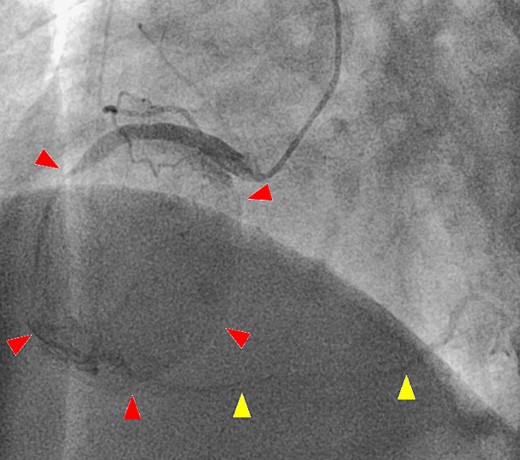

A 52-year-old man with transient ischemic attack was transferred to our hospital. He had a history of hypertension and dyslipidemia. He was conscious and had no particular symptoms after arriving at our hospital; however, an electrocardiogram showed ST-segment elevation in leads II, III, aVF, and V1–4. Enhanced computed tomography revealed a giant CAA at the RCA (Fig. 1). The aneurysm measured 50 mm in diameter and was completely occluded by a thrombus. Additionally, the coronary artery distal from the CAA did not show contrast. Emergency coronary angiography was performed. The RCA was occluded at segment #2 proximal to the CAA, and the CAA did not show contrast (Fig. 2A); however, the artery distal to the CAA showed contrast via a collateral artery from the left circumflex artery (Fig. 2B). Anticoagulation therapy involving intravenous heparin was started. After several hours, the ST-segment elevation disappeared quickly, and there were no particular symptoms. The creatine kinase level spiked to a maximum of 1475 IU/L, which then decreased to 432 IU/L on the next day. Four days after starting therapy, enhanced computed tomography and coronary angiography were performed again. They showed slight contrast in the CAA and the distal coronary artery (Fig. 3). Thus, surgery was performed to prevent the CAA from rupturing.

A second coronary artery angiography shows slight contrast in the aneurysm (arrow head) and in the distal coronary artery (arrow head).